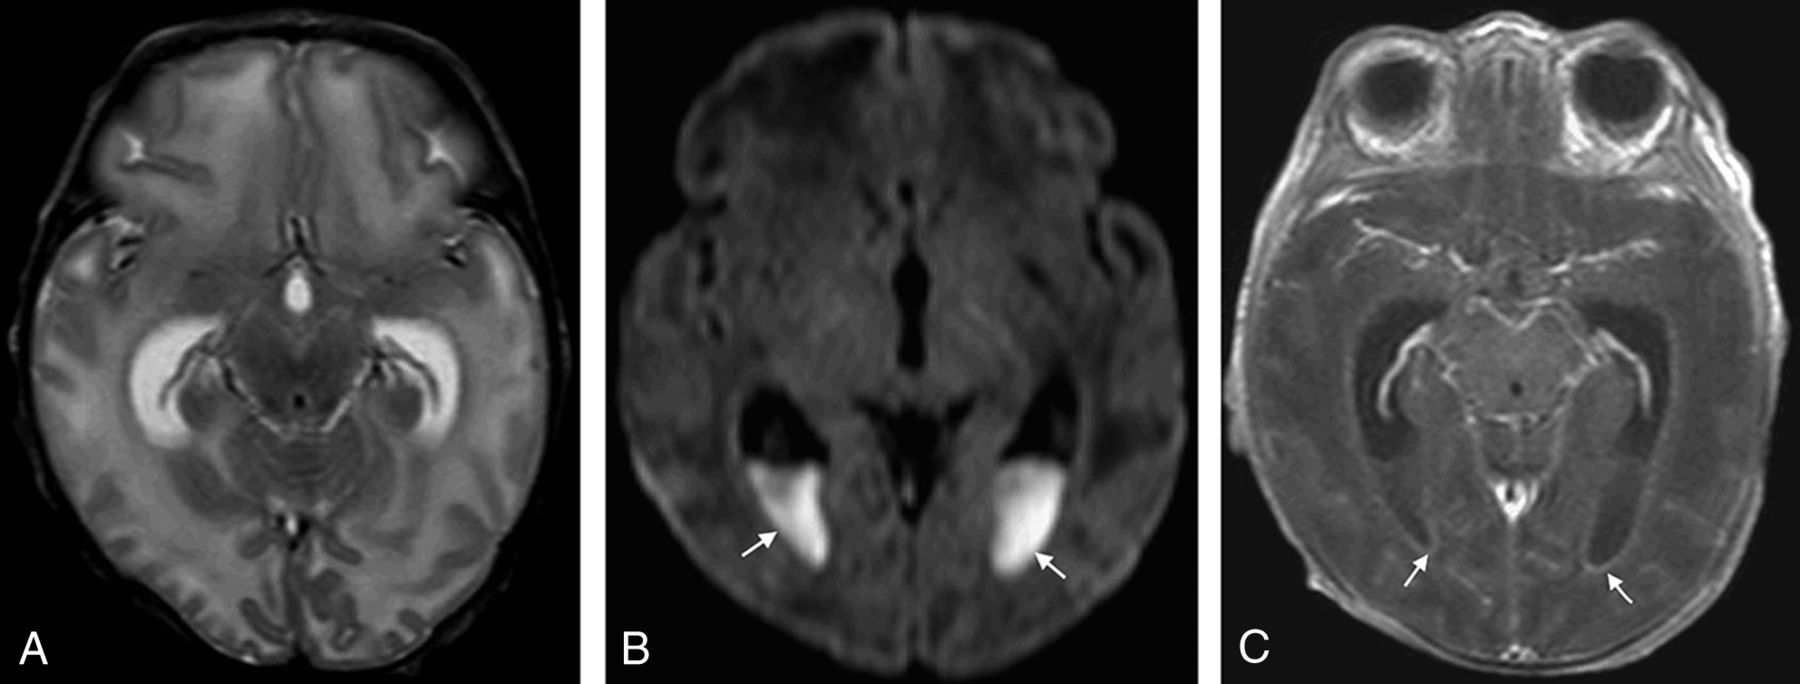

There was no statistically significant difference between groups for the duration from presentation to the date of MR imaging (10.1 versus 12.8 days, P = .08). There was a significant difference between GBS and E coli meningitis for acute development of hydrocephalus (0% versus 22%, P = .001). Ultimately, 7% (4/57) of patients with GBS meningitis required ventriculoperitoneal shunting compared with 18% (9/50) of patients with E coli meningitis (P = .14). There was a shorter mean time to development of hydrocephalus among patients with E coli meningitis compared with those with GBS meningitis (18 versus 92 days; P = .006). There was a significant difference between GBS and E coli meningitis for the development of infarct (40% versus 14%; P = .038). There was no statistically significant difference between GBS and E coli groups for leptomeningeal enhancement, cerebritis, ependymal enhancement, abscess/granuloma, subdural effusion, hemorrhage, extra-axial purulent material, intraventricular purulent material restriction, or sinus thrombosis. Representative examples of patients with GBS and E coli meningitis are seen in Figs 1 and 2.

A 19-day-old neonate with E coli meningitis. A, Axial T2-weighted image demonstrates disproportionate enlargement of the lateral ventricles relative to the sulci, consistent with hydrocephalus. B, Axial DWI demonstrates areas of diffusion restriction (ADC not shown) in the ventricles (arrows), consistent with intraventricular purulent material. C, Axial T1-weighted postcontrast image demonstrates abnormal ependymal enhancement along the lateral ventricles (arrows).